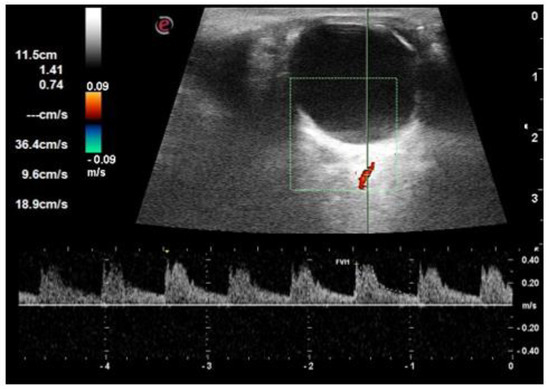

| PSV short posterior ciliary arteries (cm/s) | 19.1 ± 2.5 | 18.0 ± 4.2 | 16.7 ± 4.9 | 0.030 |

| EDV short posterior ciliary arteries (cm/s) | 5.9 ± 0.7 | 5.1 ± 1.3 | 4.3 ± 1.0 | <0.001 |

| RI short posterior ciliary arteries | 0.69 ± 0.03 | 0.71 ± 0.03 | 0.73 ± 0.5 | <0.001 |